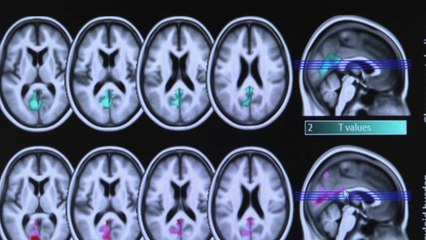

Elle augmenterait les risques d’apparition d’Alzheimerbr L’Alzheimer favorise le diabète, l’obésité et d’autres troubles. Une étude américaine publiée en novembre 2017 pointe aussi du doigt un lien entre elle et la formation de dépôts d’amyloïdes. Plus l’apnée du sommeil est sévère, plus les dépôts sont importants. Or, ils produisent des protéines toxiques, endommageant les cellules cérébrales. Ce mécanisme pourrait déclencher la maladie d’Alzheimer.br br Elle accélère aussi le déclin cognitifbr Une autre étude américaine, publiée en avril 2015 dans « Neurology », révèle que l’apnée du sommeil accélère le déclin cognitif déjà présent. On peut supposer que la mauvaise oxygénation du cerveau et l’accumulation de dépôts d’amyloïdes sont en cause. Mais les mécanismes restent à démontrer clairement. A noter : bien soignée grâce au port d’un masque PPC durant la nuit, l’apnée du sommeil ne présenterait plus de risque particulier d’Alzheimer.